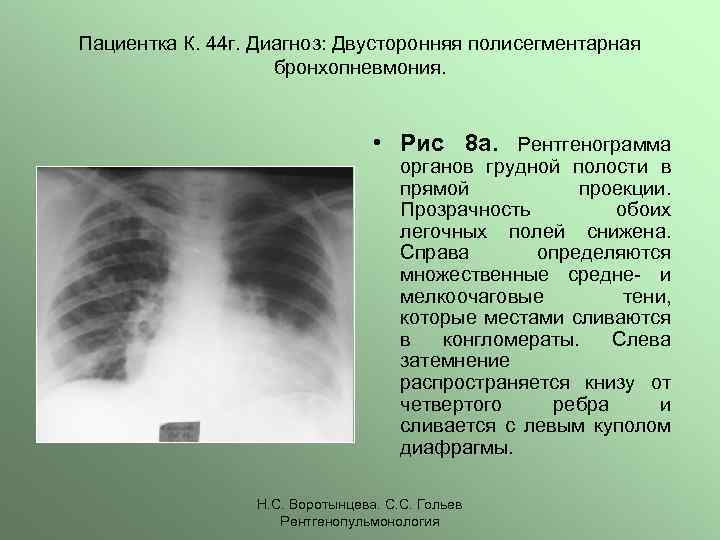

Рентгенодиагностика бронхопневмонии: Советы и примеры

Раздел: Альбом открытий